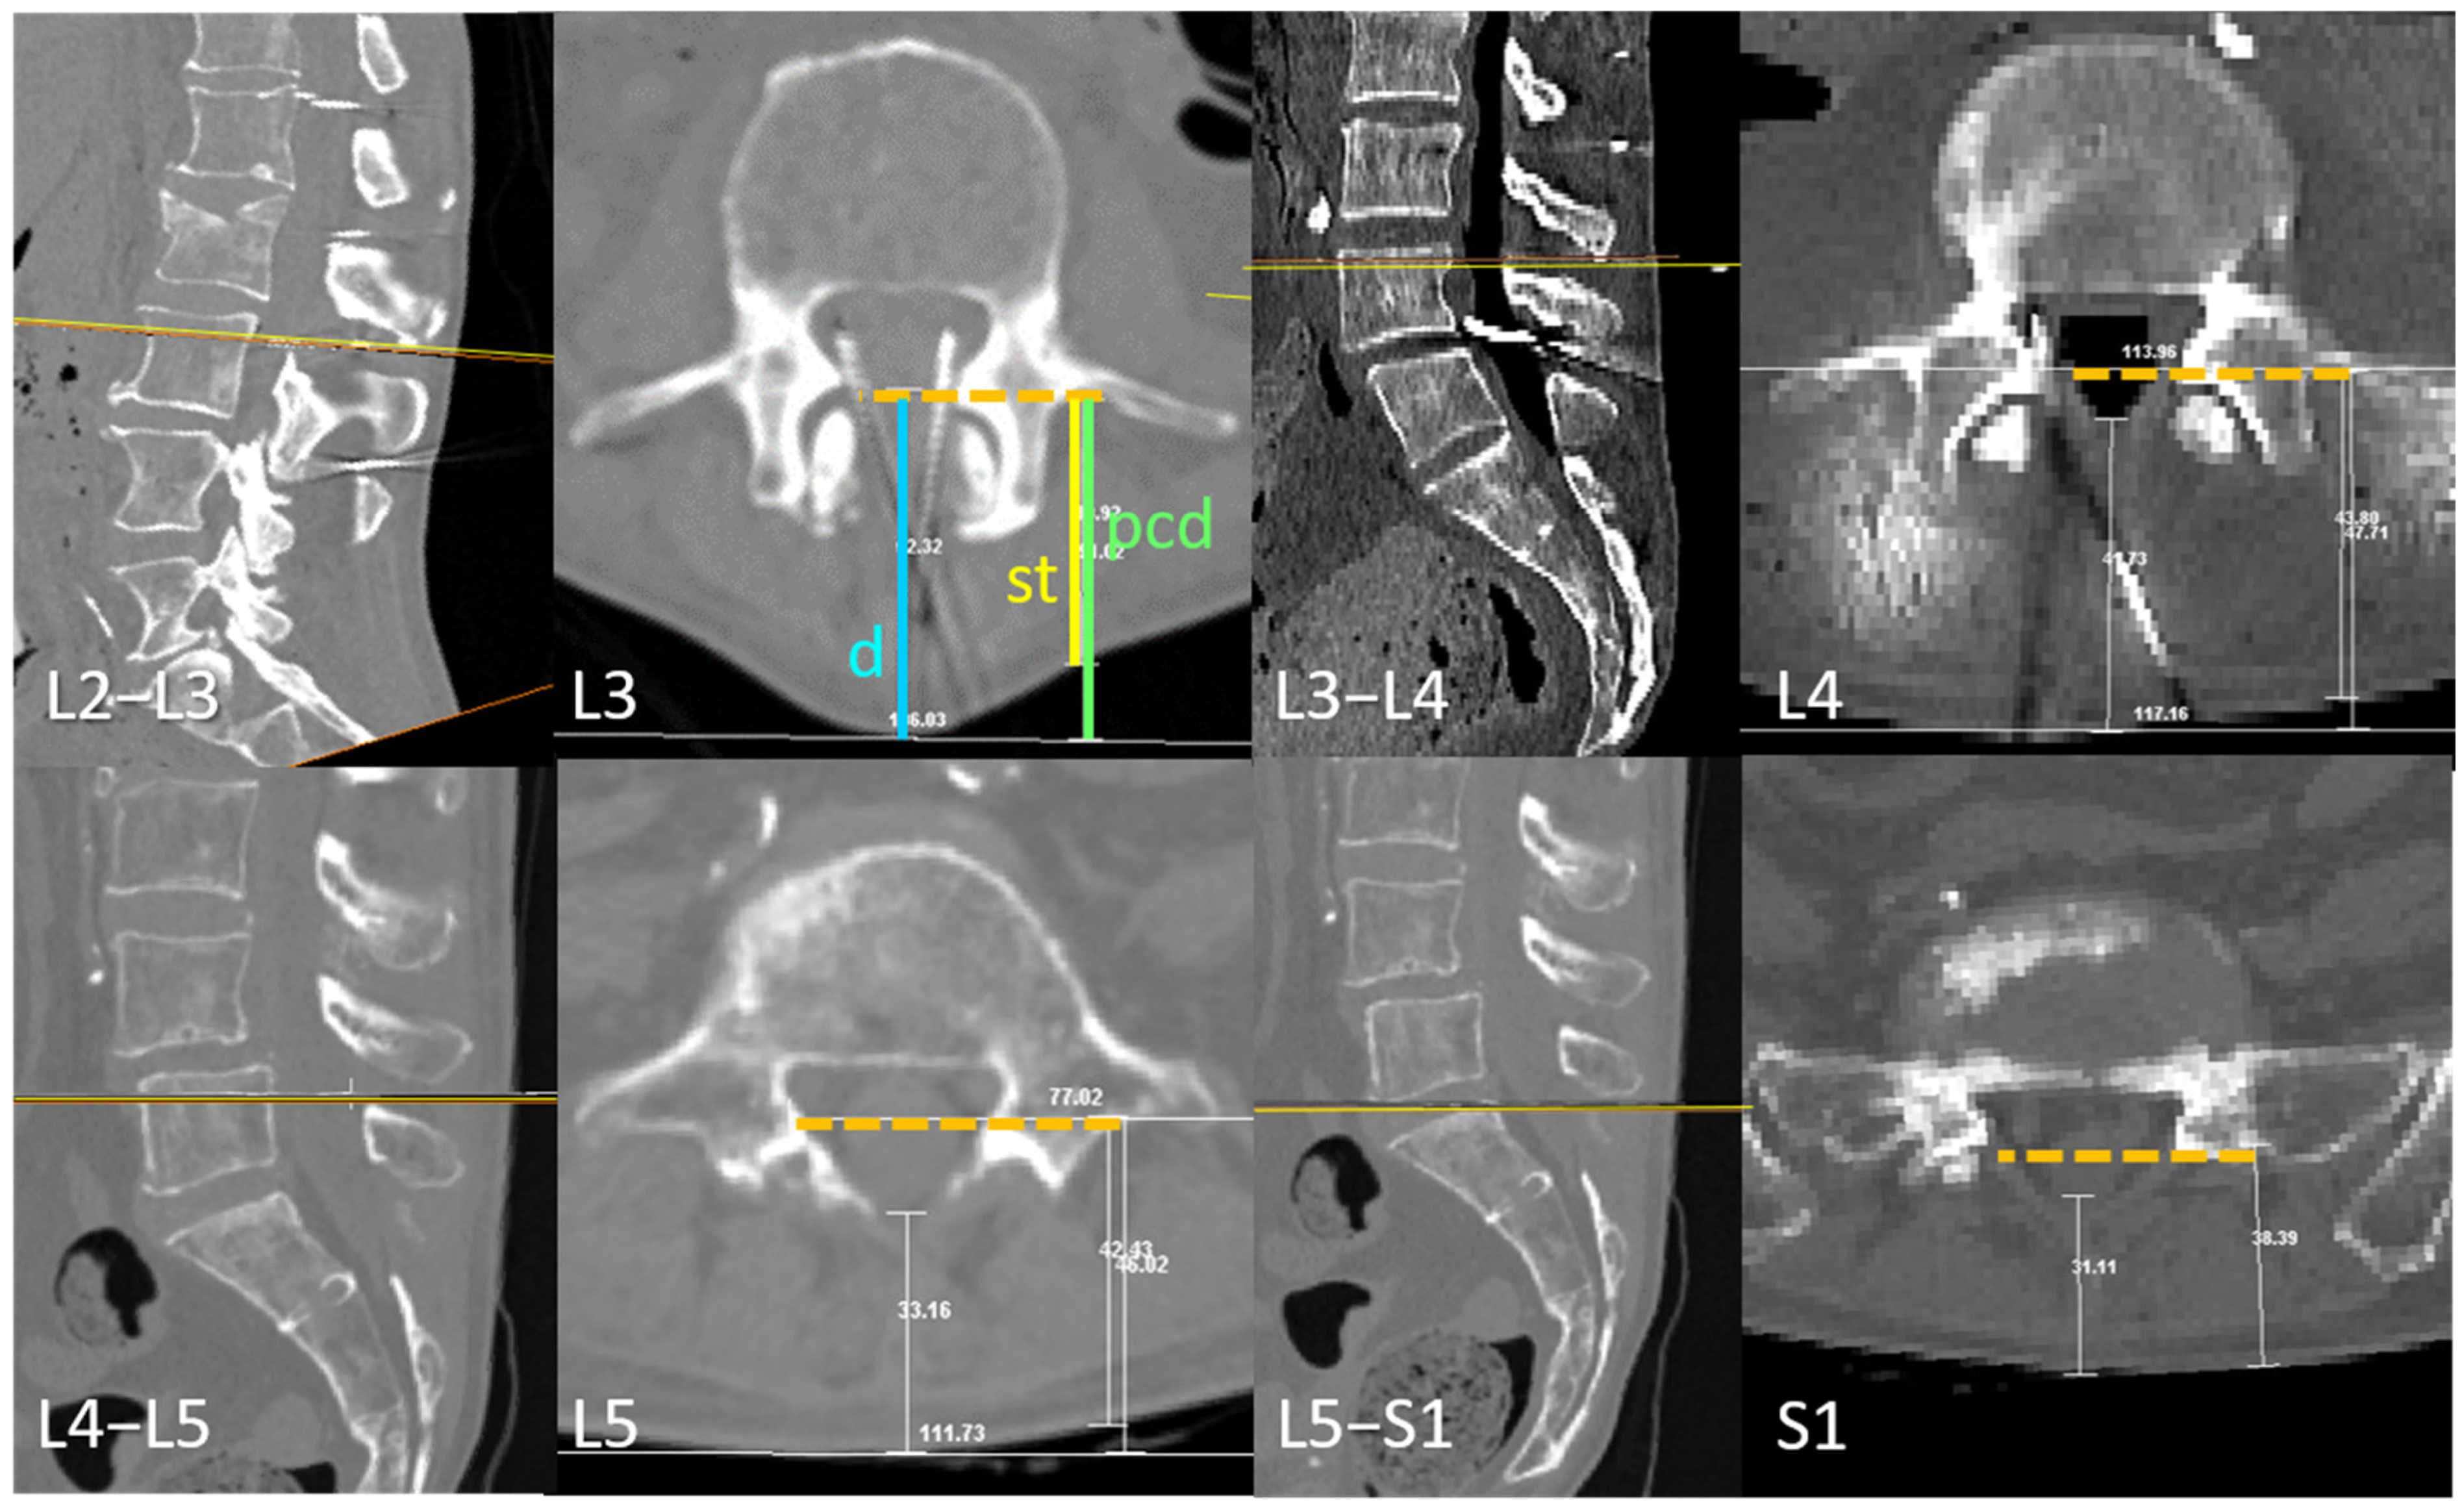

2.1.1. Transverse Process and Dural Sac Alignment

3.1. Transverse Process and Depth Level Within the Dural Sac